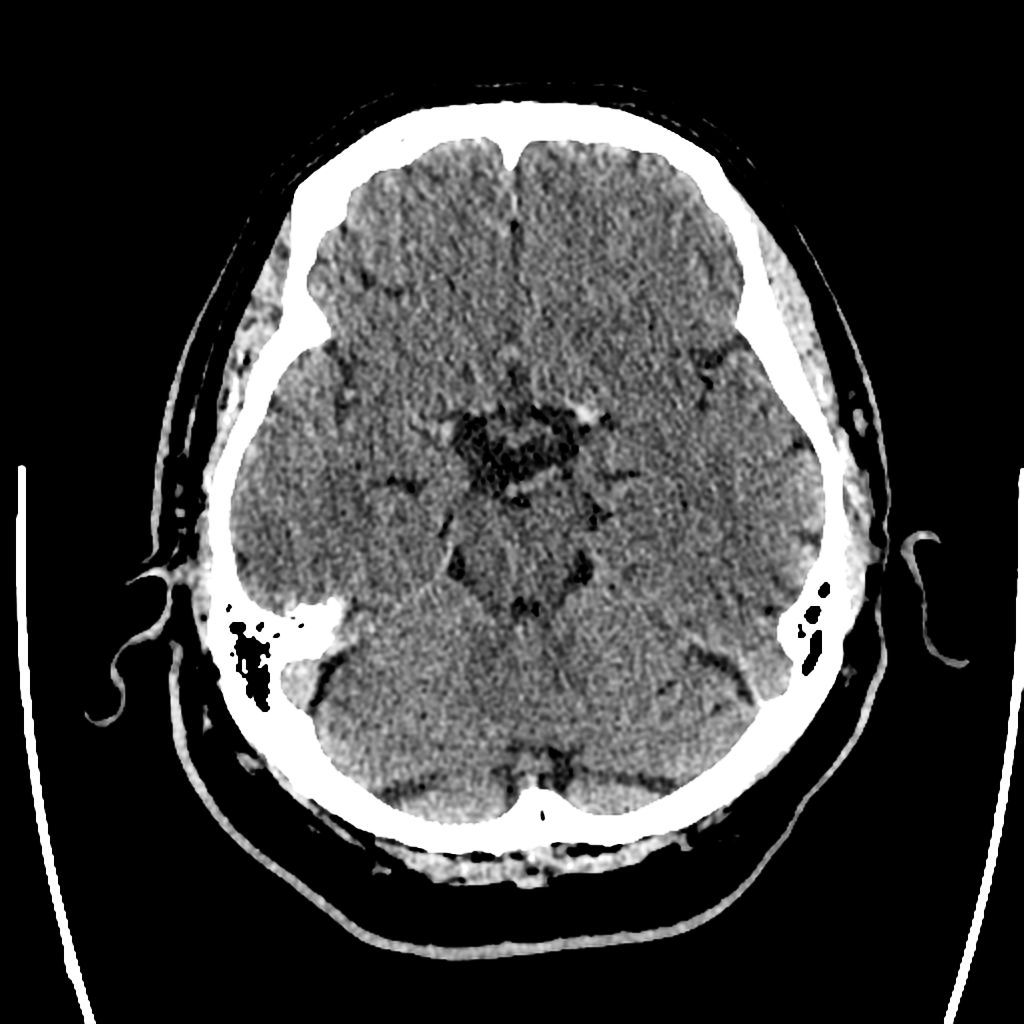

AVC : hyperdensité spontanée de l’artère sylvienne gauche

AVC : hyperdensité spontanée de l'artère sylvienne gauche

Case courtesy of Dr Henry Knipe, Radiopaedia.org. From the case Acute left MCA territory ischaemic stroke